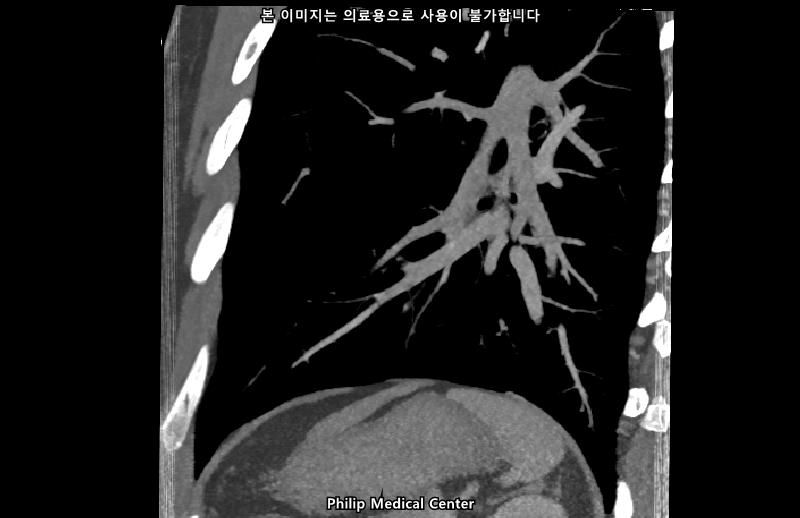

• 2번 째 사진

• 올리신 사진들을 통해서는 폐를 평가할 수 없습니다.

우측 폐첨부에 경미한 섬유성변화와 우중엽에 약 3mm크기의 결절이라는 것은 이상 소견이긴 하지만 보통 경과관찰을 하는 소견입니다.